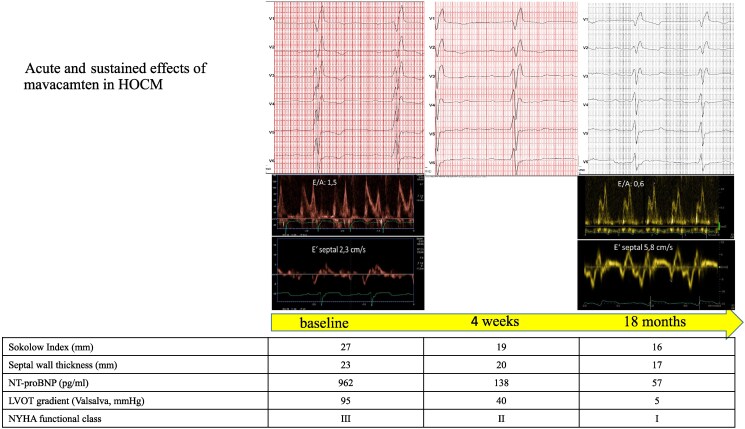

Case summary: This report highlights the effects of myosin inhibition in a 72-year-old male patient with symptomatic hypertrophic obstructive cardiomyopathy. The patient was refractory to standard medical as well as interventional therapies (myectomy and septal ablation). Initiation of mavacamten therapy led to marked clinical improvement, including increased exercise capacity and weight loss due to improved physical activity. Echocardiography revealed regression of septal wall thickness, reduction of the left ventricular outflow tract gradient, and improvement of diastolic function. Furthermore, electrocardiogram changes consistent with hypertrophyincluding voltage criteria and T wave inversions-resolved completely. The cardiac biomarkers have normalized.

Discussion: Myosin inhibition has the potency to reverse multiple pathophysiological mechanisms in hypertrophic obstructive cardiomyopathy-even in patients with advanced age and with long-standing, resistant, and symptomatic disease. The treatment effects could be observed rapidly.